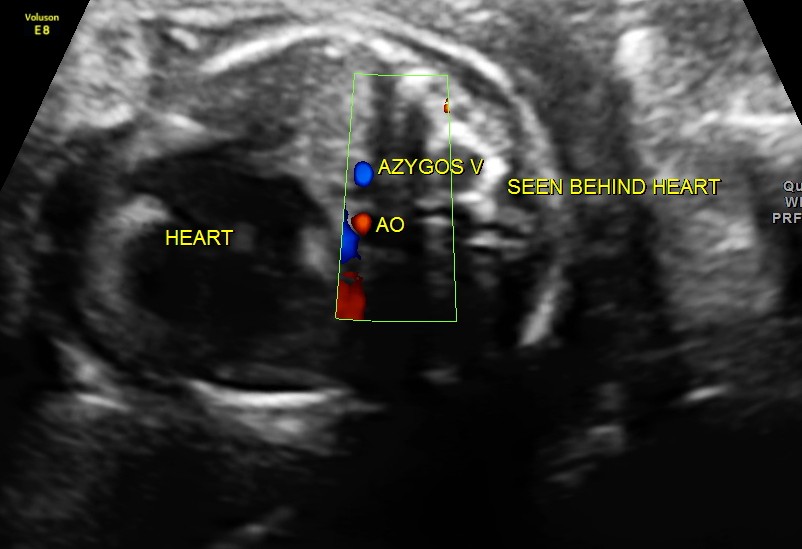

Particular to the diagnosis of Left isomerism or polysplenia syndrome is the demonstration of inferior vena caval interruption with azygos continuation.

double vessel sign seen in front of spine

double vessel sign seen behind the heart

1. double vessel sign of aorta and azygos vein running side by side , with azygos slightly posterior,